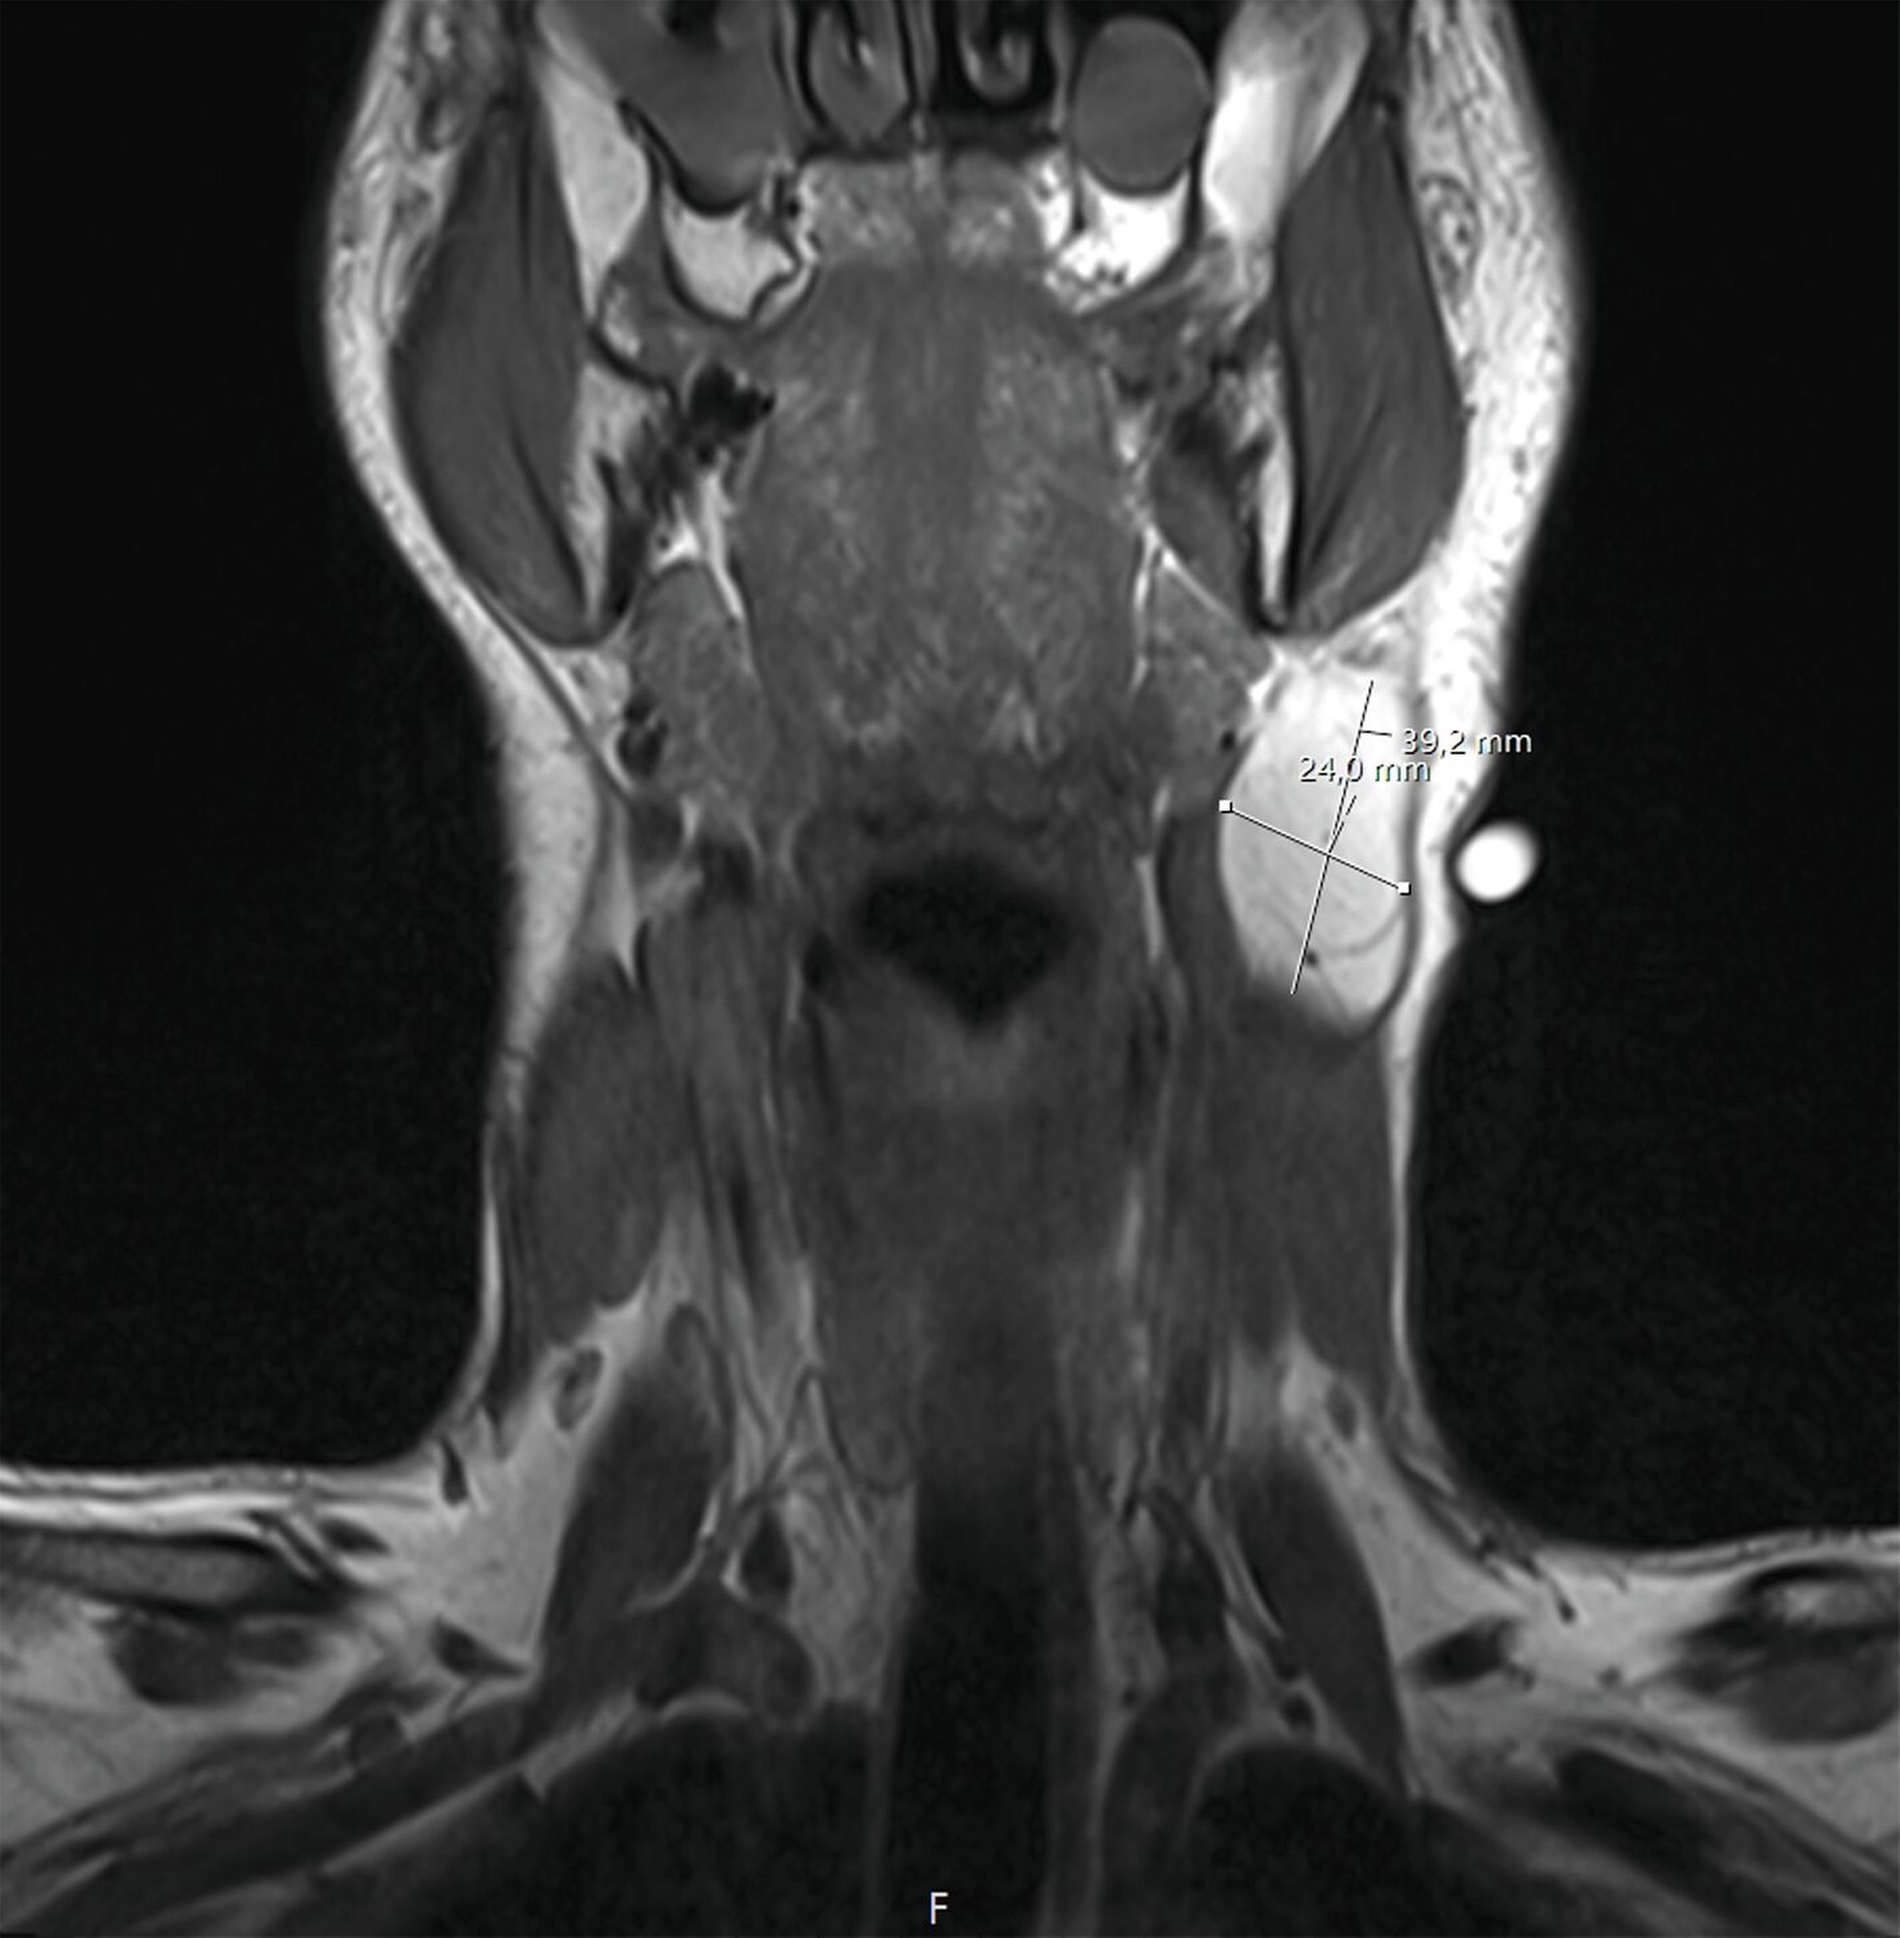

Bereits zum damaligen Zeitpunkt hatte der Patient einen niedergelassenen Kollegen mit der Bitte um Mitbeurteilung aufgesucht. Eine daraufhin angefertigte Magnetresonanztomografie zeigte einen circa 24 mm x 40 mm großen Befund im Bereich des mittleren Halsdreiecks, der keine Zeichen von Infiltration im Bereich der Gefäße oder der umgebenden Muskulatur aufwies (Abbildung 2).